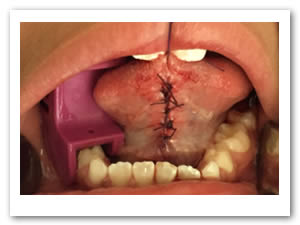

• Se irrigó bien la zona operatoria con solución fisiológica, se secó con gasa estéril, se revisó la hemostasia encontrándose en condiciones normales y se realizaron puntos simples de sutura utilizando Vicryl 3-0. Se terminó el acto quirúrgico sin accidentes ni incidentes. Figuras 11 y 12.

Figuras 11 y 12. Sutura y terminado del acto quirúrgico.